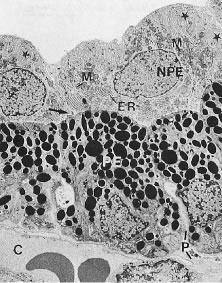

As noted earlier, the two cell layers that constitute the ciliary epithelium are named for their relative content of melanin pigment. The layer closest to the ciliary body stroma is the pigmented ciliary epithelium and that closest to the posterior chamber of the eye is the nonpigmented ciliary epithelium (Fig. 11). The morphology of the ciliary epithelium varies along the surface of the ciliary body, in accord with the different demands placed on it in various locations.1 From this analysis, it appears that it is primarily the epithelia at the tips of the ciliary processes that are involved in the production of aqueous humor. In these areas, immunoelectron microscopic studies have clearly documented both Na-K-ATPase activity (Fig. 12) and carbonic anhydrase activity11,12 (Fig. 13). Both are known to be central to the production of aqueous humor and one of them, carbonic anhydrase, is regularly targeted for pharmacologic inhibition to reduce intraocular pressure in glaucoma.13

Fig. 11. Electron micrograph of the ciliary epithelium (cynomolgus monkey, pars plicata). The posterior chamber is at the top and the ciliary body stroma, with its fenestrated capillaries (C), is at the bottom. Extensive basolateral infoldings of the nonpigmented ciliary epithelial cells (NPE) are evident (stars). The apical surfaces of both layers face one another (arrow). PE, Pigmented ciliary epithelium; M, mitochondria; ER, endoplasmic reticulum; P, paracellular space. (Lütjen-Drecoll E: Functional morphology of the ciliary epithelium. In: Lütjen-Drecoll E (ed): Basic Aspects of Glaucoma Research. Stuttgart, Germany: FK Schattauer, 1982, p. 79.)